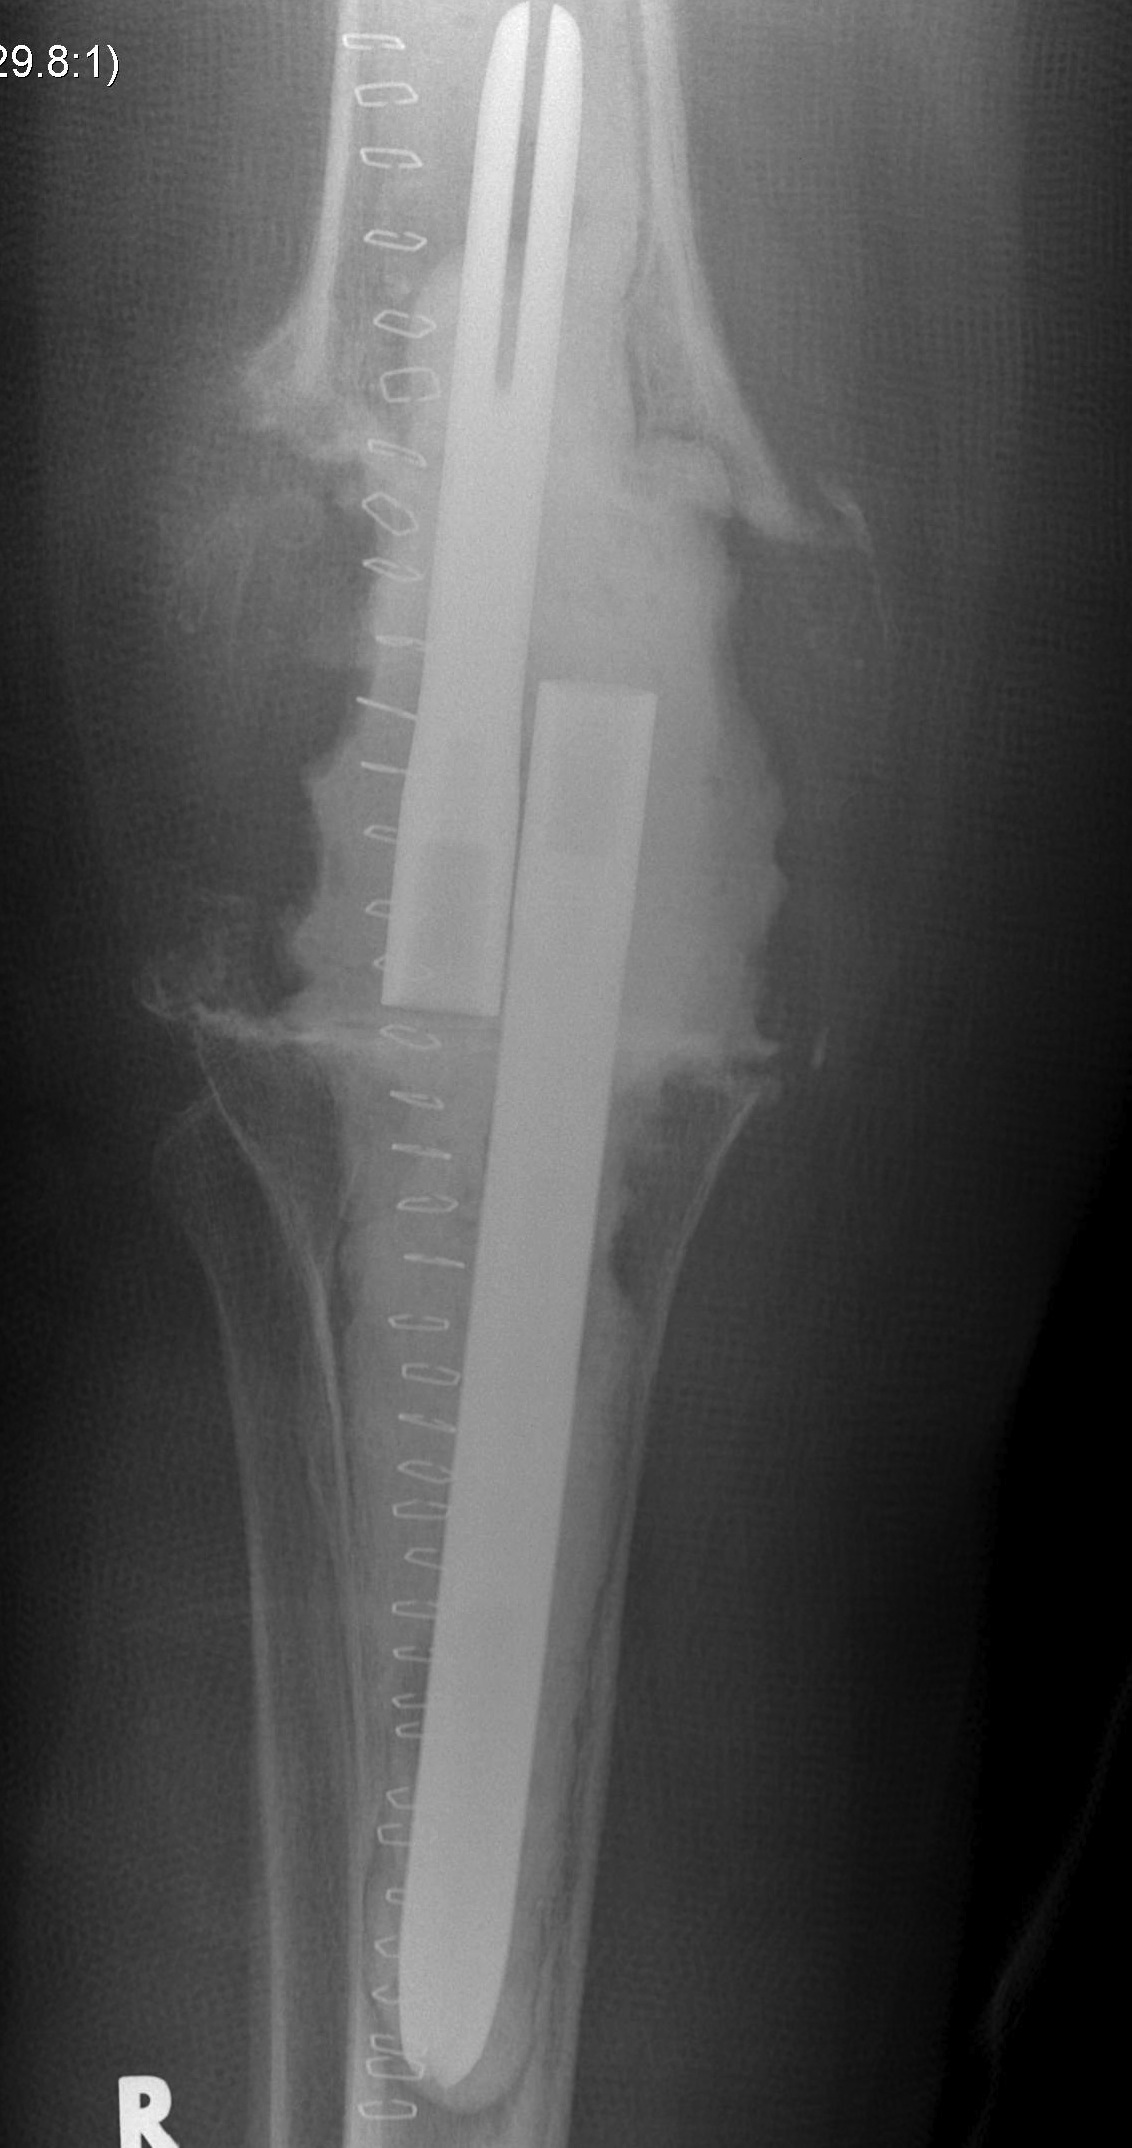

- 184 cemented revision TKR with press fit stems

- 7% revision rate for deep infection

- significant bone loss

10. Loosening